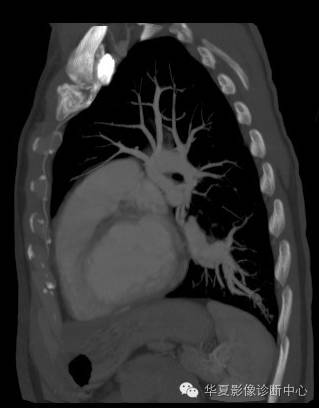

| 影像表现及分析: | 影像表现:定位左下叶;左下叶体积缩小,整体密度增高,支气管分布正常,其内见血管增多,但是走形正常,未见杂乱、迂曲的血管影;血管连向肺门下方软组织密度结节灶,结节与主动脉分界不清,增强后,见降主动脉发出异常粗大血管供血整个左下叶,左下肺动脉细小。 |

1、肺隔离症,一般表现为实变影,支气管不会这么畅顺、分布不会这么正常,而且易合并感染。都是体动脉供血,但供血动脉不会这么粗大。 2、肺动静脉畸形,血管是肺动脉与肺静脉,形态不规则,迂曲成团,;而这一例血管走形自然,并且属于体动脉来源,肺动脉幼小。 |

异常体动脉供应正常下肺基底段完整含义为起源于降主动脉的异常动脉供应下肺基底段,而基底段支气管树和肺实质正常,同时基底段肺动脉缺如或狭窄【大部分缺如(完全型),部分狭窄(不完全型)】;95%以上累及左下肺,因此也称为异常体动脉供应正常左下肺基底段。 病因尚未明确,可能是胚胎发育时期供应肺芽的背主动脉原始小分支退化不全,与肺实质形成异常连接,并影响肺动脉与肺血管床连接而导致此部位肺动脉发育不良,而支气管、肺组织的发育未受影响。本病的病理生理基础为左向左的分流,体动脉供应的肺组织充血,体循环的高压可增加肺血管床的压力和左心负荷,同时也增加肺循环量和压力而增加右心负荷,导致各种临床症群。本病可无临床症状,部分患者可有咯血、呼吸道感染、呼吸困难、充血性心力衰竭。 影像表现:左肺下叶体积缩小,整体密度稍增高,支气管树走形、分布正常,血管增多、稍增粗;增强后显示左下肺动脉幼小,甚至不发育;下叶由主动脉发出的粗大血管供血。 |